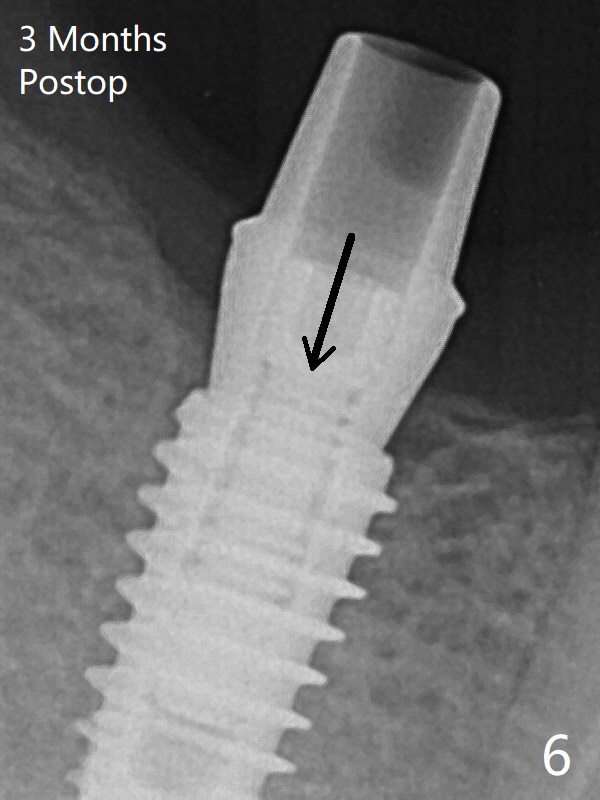

The female patient has limited mouth opening, complicated further by supraerupted opposing tooth. It is difficult to insert point drill and tap drill for #30 implant placement with guide. The former has to be inserted into the sleeve of the guide extraorally; two of them are placed intraorally together, while the tap drill is not used at all. When a 4.5x10 mm implant is placed, it is difficult to use #2 sensor to take PA. Finally a BW is taken with #2 sensor (Fig.1), while a PA is taken with #1 sensor (Fig.2). CT is taken to show clearance of the implant from the Inferior Alveolar Canal (Fig.3,4). To seat healing and later cemented abutments completely, a 5.5 mm profile drill is applied after implant placement; the outline is illustrated by red dashed line in Fig.1''. The elongated mesiolignual cusp of the tooth #3 has to be trimmed after placement of a 6x5 mm healing abutment. In fact trimming prior to osteotomy could solve the mouth opening partially. After removal of the 6x5 mm healing abutment, a 4.5x4(3) mm cemented abutment is incompletely seated (Fig.5 <) apparently due to proximity to the mesial crest (*). With reuse of a 4.6 mm profile drill, the abutment is fully seated (Fig.6), confirmed clinically by more clearance from the opposing tooth (Fig.7). Complete occlusal clearance is obtained by reduction of the opposing cusps without sensitivity since the tooth is nonvital (*). Return to No Deviation Xin Wei, DDS, PhD, MS 1st edition 05/28/2020, last revision 09/04/2020